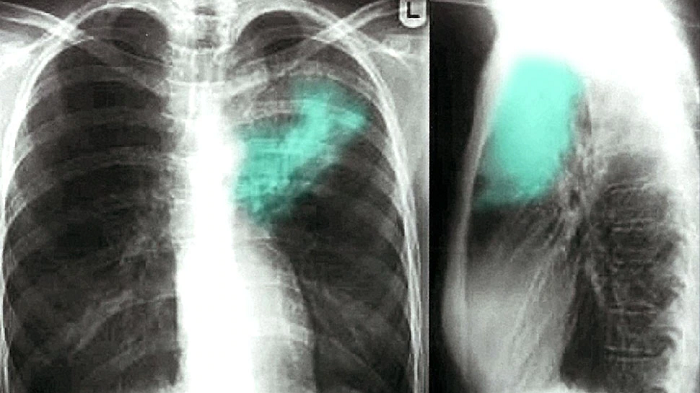

डॉक्टर ने महिला को टीवी की बीमारी मानकर जब जाँच शुरू की तो महिला की रिपोर्ट हमेशा निगेटिव आती थी. जिससे डॉक्टर भी चौक जाते थे की आखिर महिला को हुआ क्या है. ऐसे में डॉक्टरों ने महिला के फेफड़े का एक्सरे कराया और पाया की महिला के दाहिने ओर सूजन है. इसके बाद डॉक्टर को एक्सरे में कुछ बैग टाइप का दिखाई दिया। जिसे देखकर डॉक्टर भी चौक गए.

डॉक्टरों ने महिला का ऑपरेशन करने का निर्णय लिया और पाया की महिला के अंदर कंडोम (Condom) था. जिसे देखकर डॉक्टर खुद दंग रह गए. डॉक्टरों ने जब इस बारे में पति-पत्नी से पुछा तो उन्होंने स्वीकार किया की मुँहमैथुन के दौरान कंडोम महिला के मुँह से अंदर चला गया था. जिसके बाद उन्होंने शर्म के मारे किसी को नहीं बताया जबकि उन्हें सब पता था.